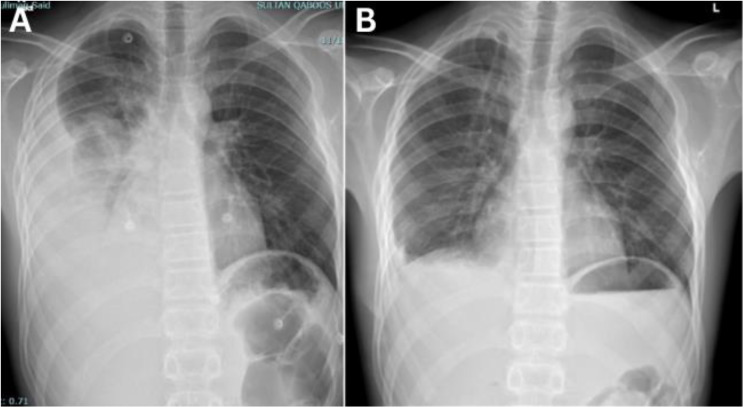

Exostosis, or osteochondroma, is an irregular bone growth commonly occurring near the femur, scapula, humerus and ribs. It can be a single isolated lesion or multiple lesions as in hereditary multiple exostoses (HME) which is a genetic autosomal dominant disorder. Although often asymptomatic, complications such as haemothorax are rare and have serious implications if not promptly recognised. We report a 15-year-old male patient who presented to a tertiary care hospital in Muscat, Oman, in 2023 who presented with progressive chest pain and dyspnoea. The patient had a family history of HME. Video-assisted thoracoscopic surgery (VATS) confirmed the osteochondromatous lesions on the 8th rib, which was causing the haemothorax. The lesion was resected and post-surgery, the symptoms resolved. No recurrence was documented up to the time of writing this report.